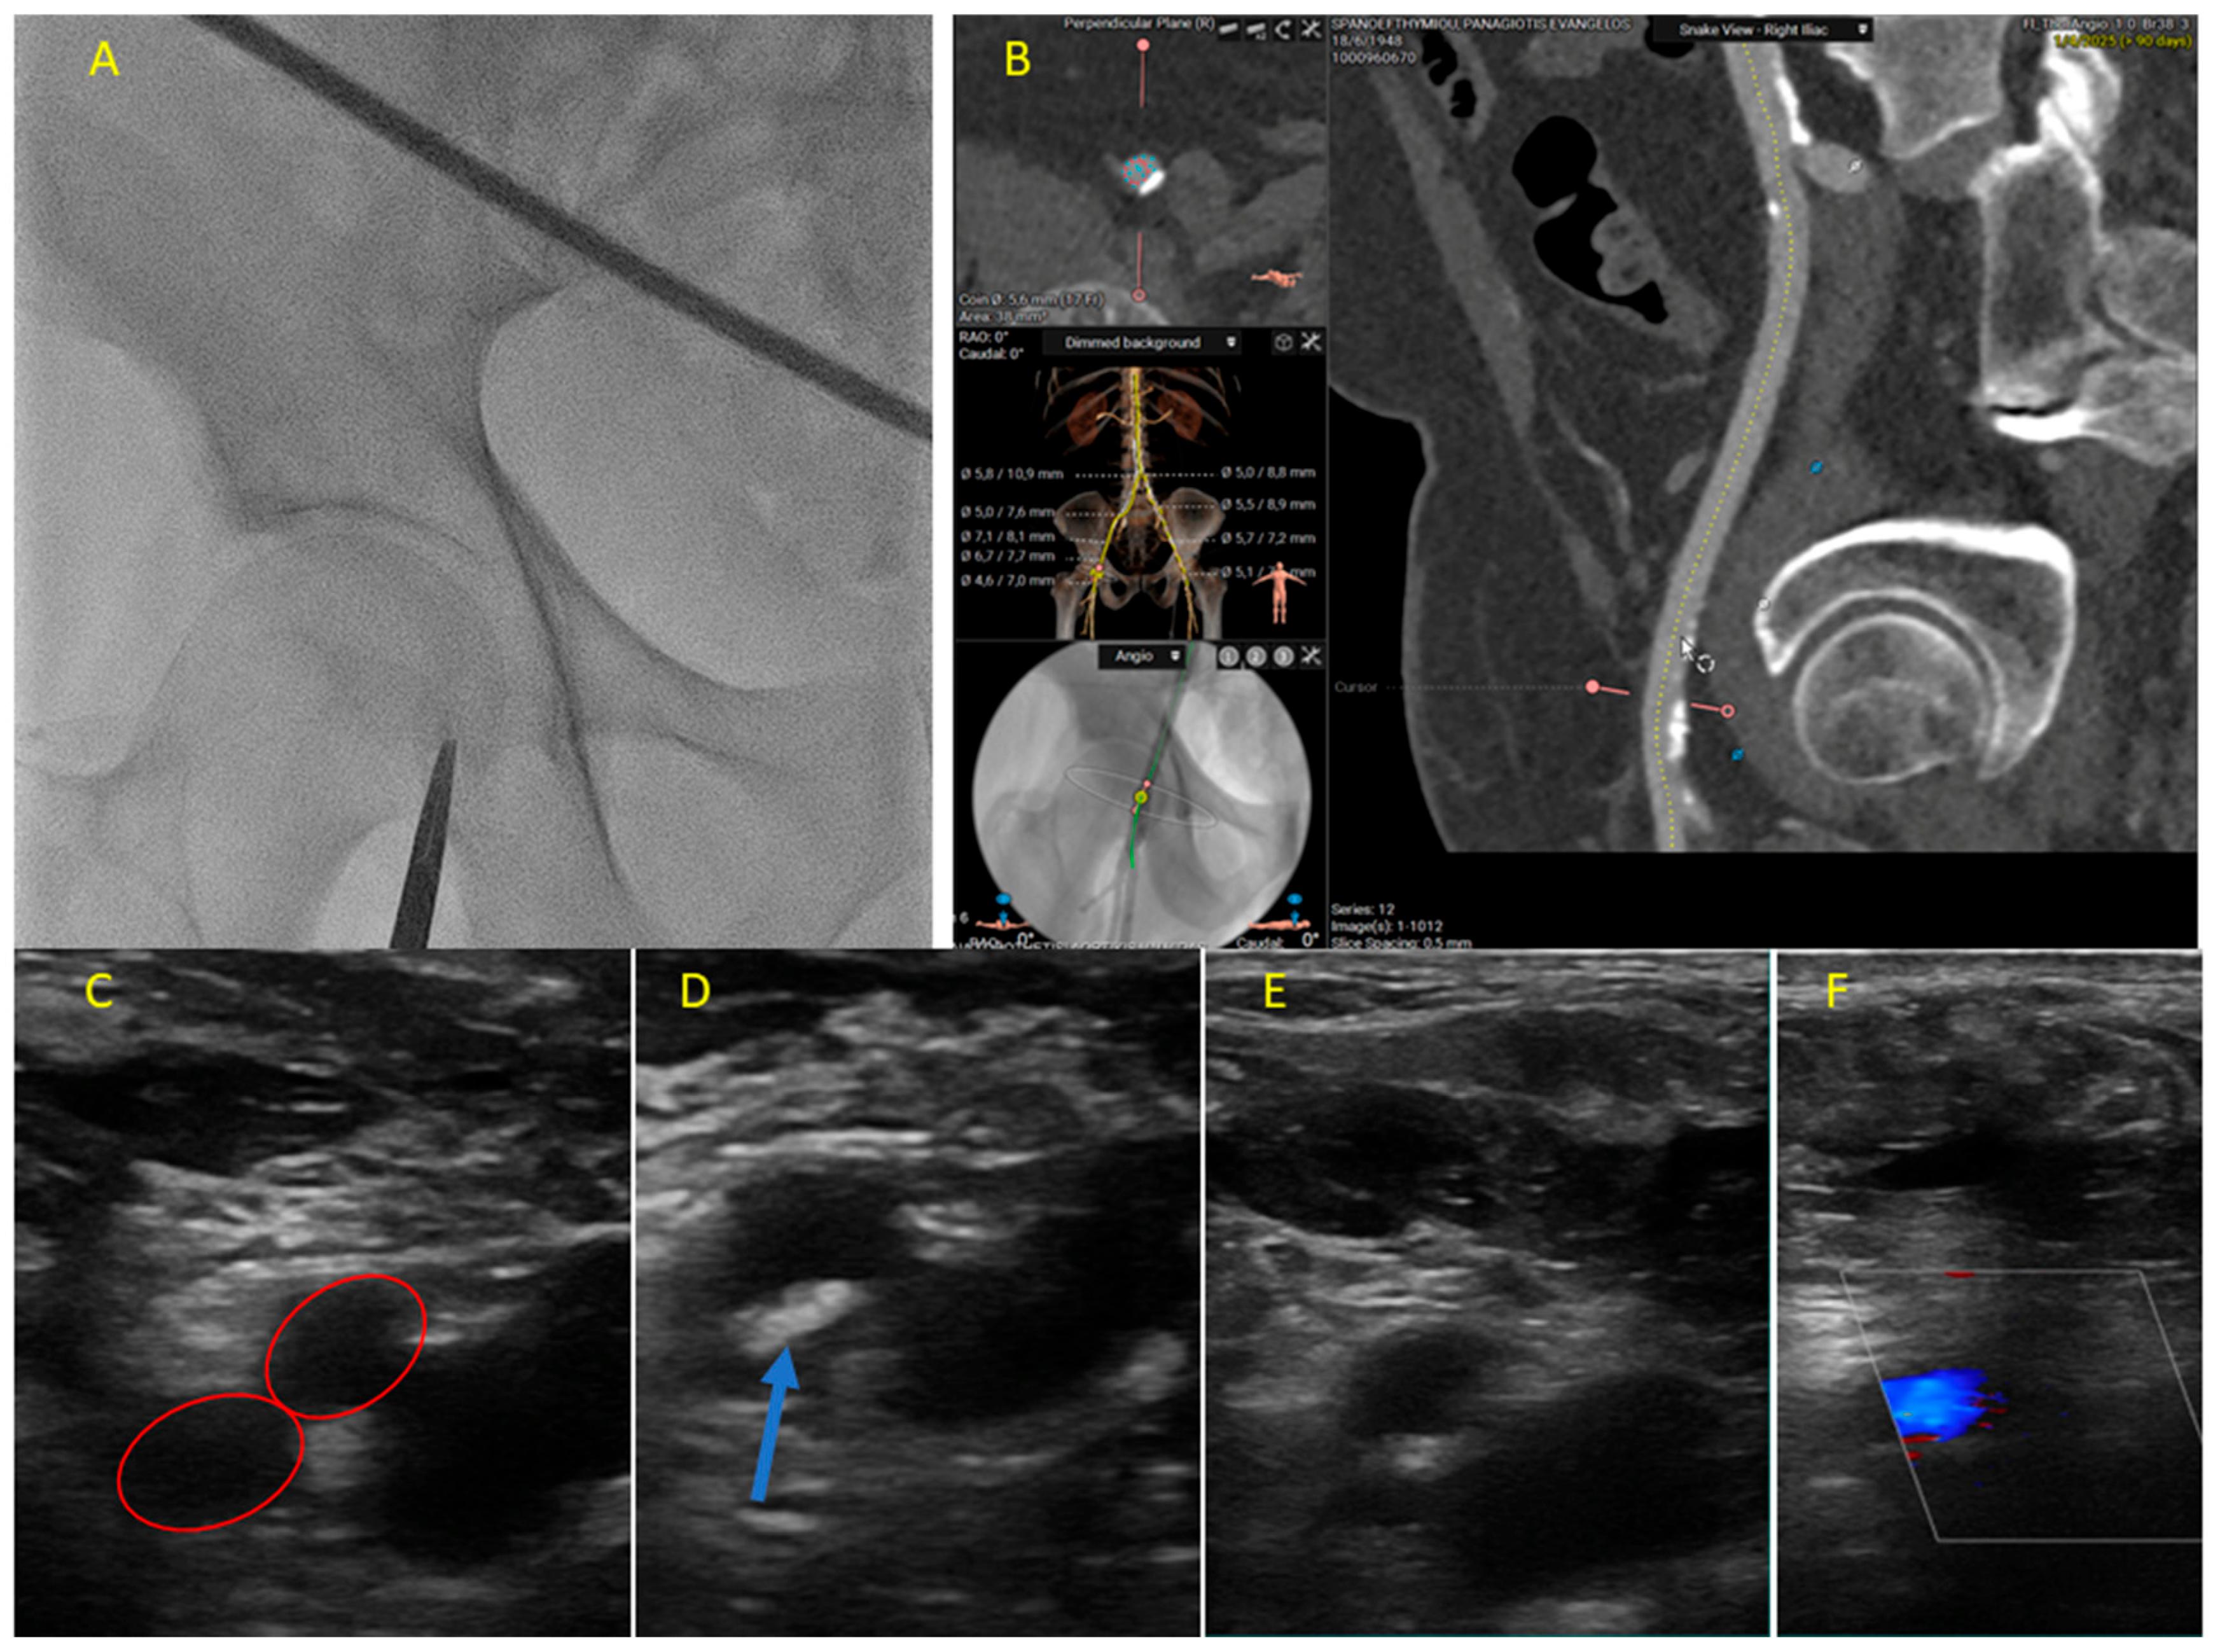

- Kotronias, R.A.; Bray, J.J.H.; Rajasundaram, S.; Vincent, F.; Delhaye, C.; Scarsini, R.; Marin, F.; Terentes-Printzios, D.; Halcox, J.P.J.; Mamas, M.A.; et al. Ultrasound- Versus Fluoroscopy-Guided Strategy for Transfemoral Transcatheter Aortic Valve Replacement Access: A Systematic Review and Meta-Analysis. Circ. Cardiovasc. Interv. 2021, 14, e010742. [Google Scholar] [CrossRef]

- Grundmann, D.; Rudolph, T.; Adam, M.; Kellner, C.; Bleiziffer, S.; Braun, D.; Tamm, A.R.; Meertens, M.; Renker, M.; Gmeiner, J.; et al. Procedural and Clinical Outcomes According to Ultrasound-Guided Access in TAVI: A Propensity-Matched Comparative Subanalysis from the PULSE Registry. Circ. Cardiovasc. Interv. 2025, 18, e014771. [Google Scholar] [CrossRef] [PubMed]

- Vincent, F.; Spillemaeker, H.; Kyheng, M.; Belin-Vincent, C.; Delhaye, C.; Piérache, A.; Denimal, T.; Verdier, B.; Debry, N.; Moussa, M.; et al. Ultrasound Guidance to Reduce Vascular and Bleeding Complications of Percutaneous Transfemoral Transcatheter Aortic Valve Replacement: A Propensity Score-Matched Comparison. J. Am. Heart. Assoc. 2020, 9, e014916. [Google Scholar] [CrossRef] [PubMed]

- Xenogiannis, I.; Varlamos, C.; Keeble, T.R.; Kalogeropoulos, A.S.; Karamasis, G.V. Ultrasound-Guided Femoral Vascular Access for Percutaneous Coronary and Structural Interventions. Diagnostics 2023, 13, 2028. [Google Scholar] [CrossRef] [PubMed]